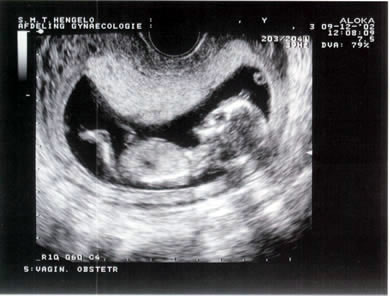

Ons kindje!

Dit vind ik persoonlijk weer de mooiste en de duidelijkste

Nog een bovenkant hoofdje en een klein handje

Mooi ruggegraatje geloof ik...